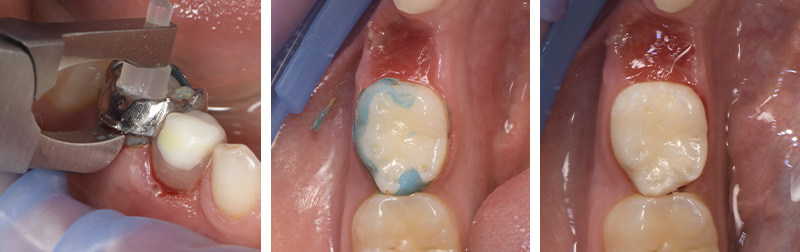

L’ajout d’un ergot sur la face vestibulaire permet une dépose facile à l’aide d’une pince dépose bague. De plus la couleur bleue du matériau d’assemblage permet également de faciliter l’élimination des résidus (aux ultras sons).

Fig. 10 : dépose du mainteneur à l’aide de la pince spécifique, élimination des excès.

Malgré l’inflammation importante sous le mainteneur lors de la dépose, au bout d’une semaine il y a une bonne cicatrisation et on peut deviner la pointe cuspidienne sous gingivale.

Fig. 11 : contrôle à 1 semaine post-dépose.